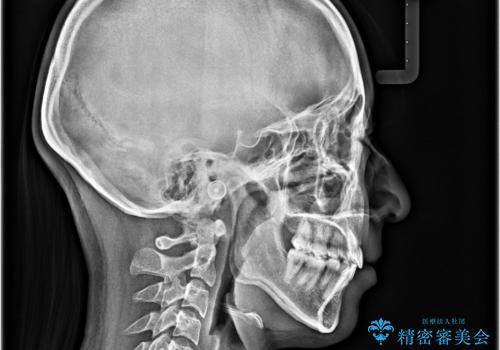

- 前歯がくちばしのように飛び出していることを気にして来院された患者様です。

唇が前方に突出している横顔が気になっているため、上下左右の第一小臼歯4本を抜歯し、ワイヤー装置にて矯正治療を行うこととしました。

わずか2年弱で一気に口元が変化し、患者様には大変満足していただけました。